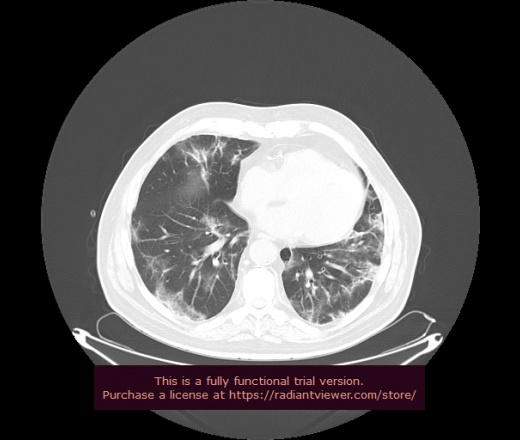

Уважаемые коллеги, если имеется интерес, сможете ли Вы спрогнозировать дальнейшее +-одинаковое течение процесса у 4 данных разных пациентов? Зацепиться где-то можно очень просто, где-то нельзя.